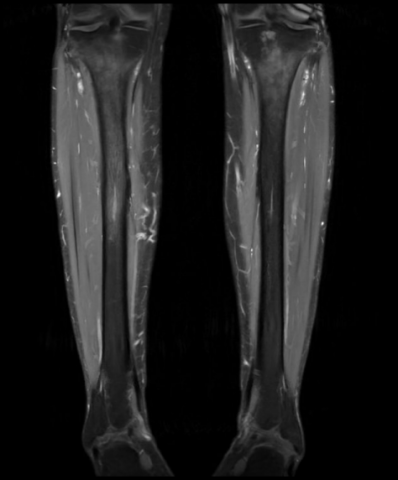

Séquence coronale.png

Séquence coronale DP FS montrant un oedème méd

ullaire tibial bilatéral, plus prononcé à droite, avec

réaction périostée.